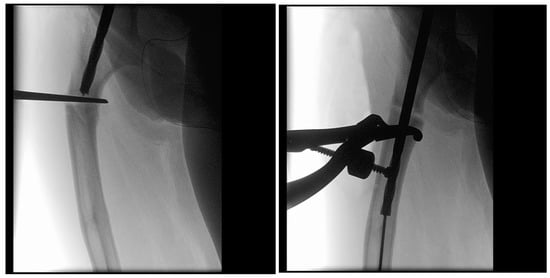

In the third case, a 16-year-old skeletally mature patient with OI was scheduled to undergo revision from FD rod to SLIM nail after presenting with pain due to stress fractures and wild deformity in his proximal right femur (Figure 11). The FD rod was removed, and then, using a piriformis entry point, access to the femur and proximal reaming was performed. There were two CORAs; the first CORA was identified in the subtrochanteric region, and a percutaneous osteotomy technique was performed to realign the bone, and then reaming was continued (Figure 12). The second CORA was identified, and another percutaneous osteotomy was performed, and the bone was cracked with a closed osteoclasis technique, and then reaming was continued in the distal segment (Figure 13). The SLIM nail was then inserted and had an excellent fit. The subtrochanteric region was under high stress, so a 2.7 Smith and Nephew EVOS plate to further stabilize the segment and control the rotation. Two screws were placed above and below (Figure 14). In this case, the indication for the use of the SLIM nail was the need to revise the existing telescoping FD rod in a skeletally mature patient to a solid nail. As the intramedullary canal was too small to accommodate a larger solid nail, a SLIM nail was used instead. The use of a plate as an adjunct to an intramedullary nail is also shown.

Figure 12.

Intraoperative X-rays showing the first CORA and alignment with the continuation of the reaming.